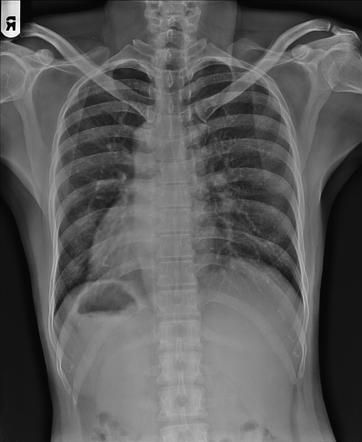

Situs Inversus refers to the transposition of thoracic and abdominal viscera. In comparison, the normal position of the viscera is referred to as situs solitus. Situs Inversus is associated with: - Dextrocardia: The incidence of dextrocardia is 3-5%. The most common association is a transposition of great vessels - Kartagener Syndrome: It is a primary ciliary dyskinesia disorder. Approximately 20% of individuals with situs inversus can have Kartagener syndrome. Situs inversus totalis can be appreciated on the chest radiography by: - The position of the gastric bubble - Location of liver - Position of the heart apex - Position of the aortic arch Reference: https://radiopaedia.org/articles/situs-inversus